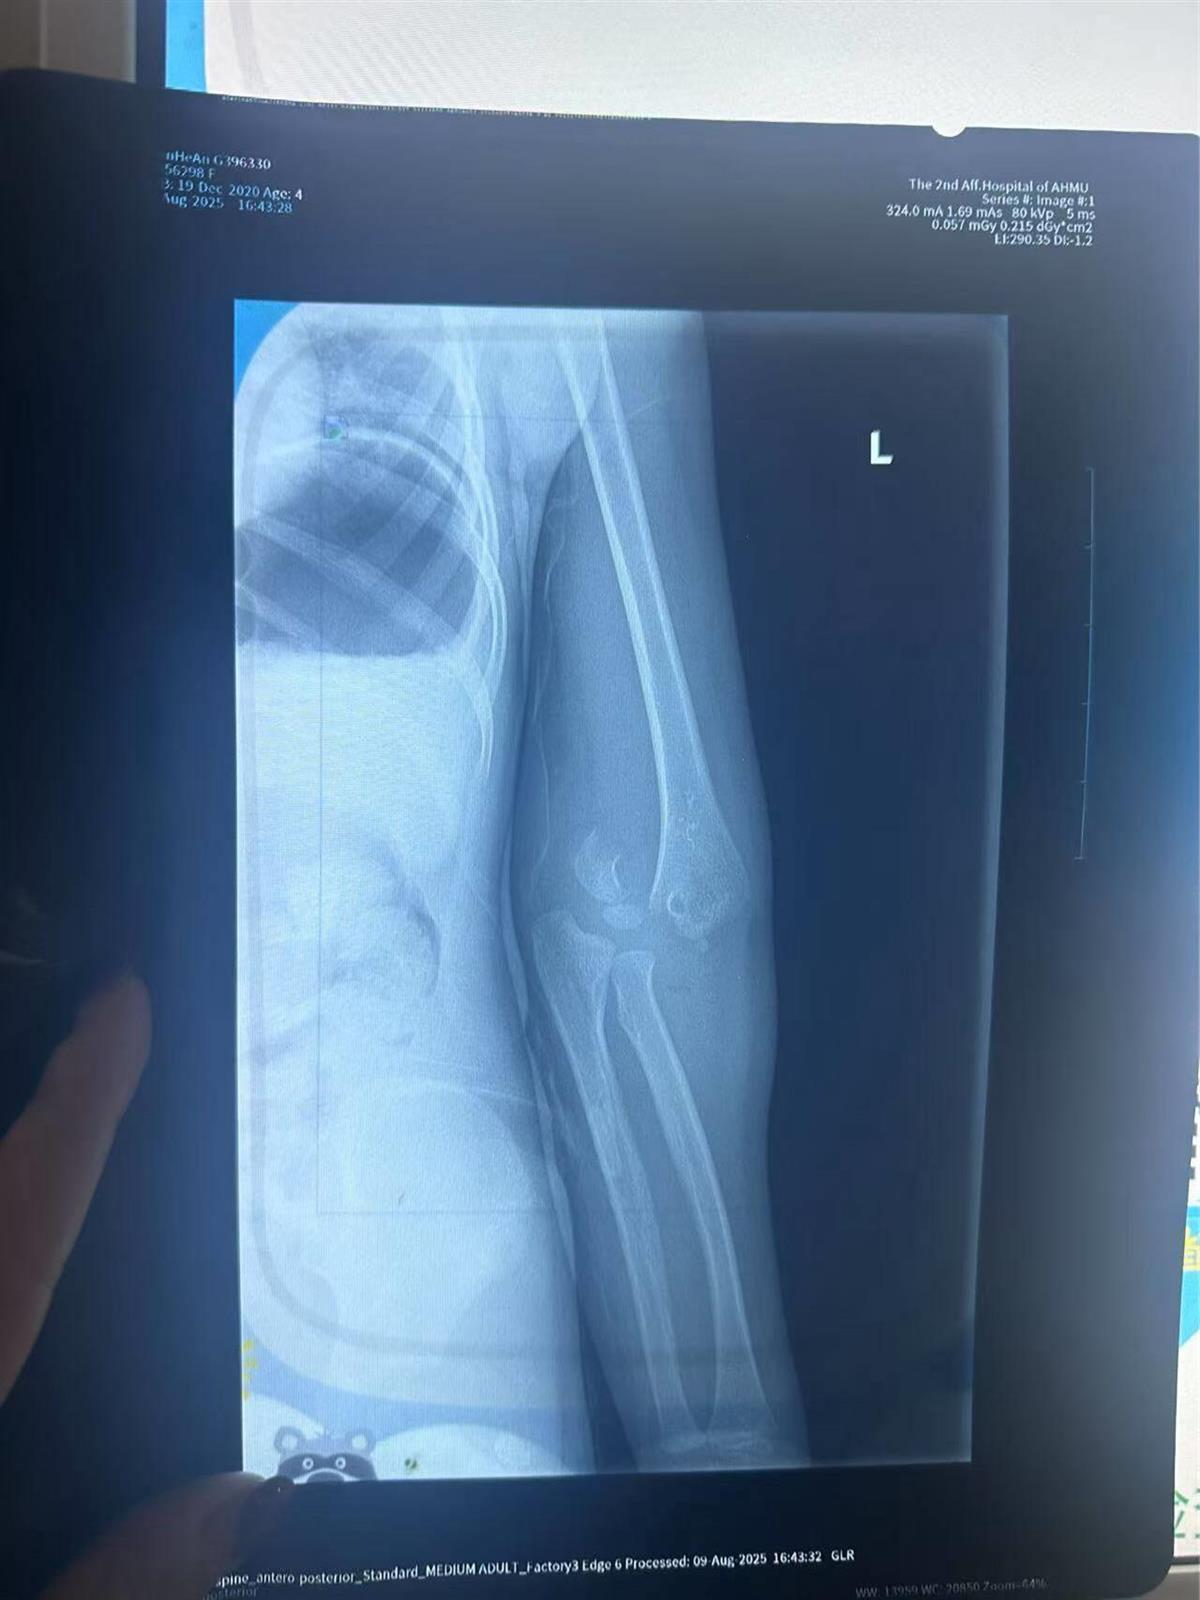

医院的诊断报告单显示,孩子“左侧肱骨远端见骨质连续性中断,可见骨折线影,断端稍分离,远端软组织内可见碎骨片影,余所示诸骨未见明显异常,肘关节在位,周围软组织肿胀”。